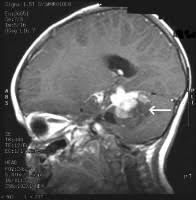

A brain stem tumor is a tumor in the part of the brain that connects to the spinal cord (the brain stem). Neurosurgeons at the brain tumor center at johns hopkins in baltimore, md, treat all types of brain tumors, including gliomas, meningiomas, pituitary tumors, and skull base tumors. A glioma will also lead to weakened muscles and a clumsy gait. Brain stem tumors, also called brain stem gliomas, can arise anywhere in the brain stem. Tumors that start in the brain are called primary brain tumors. Brain tumors are relatively common in dogs and cats. Benign brain and spinal cord tumors can affect the brain, brain stem, and spinal cord. Explore options available for astrocytomas, glioblastomas and more. The success of tumor removal; And your age and overall health. The most frequent type of germ cell tumor in the brain is the germinoma. A brain stem glioma forms in the brain stem, which is ct scan (cat scan): Your outcome is determined by such factors as the tumor's type, grade, and location;

A brain stem tumor is a tumor in the part of the brain that connects to the spinal cord (the brain stem). Neurosurgeons at the brain tumor center at johns hopkins in baltimore, md, treat all types of brain tumors, including gliomas, meningiomas, pituitary tumors, and skull base tumors. Brain tumors are found in about 2% of routine autopsies. A brain tumor is a mass formed by an overgrowth of abnormal cells. Primary brain tumors seen in dogs and cats include meningioma, glioma, choroid plexus papilloma, pituitary adenoma or adenocarcinoma, and others. A diagnostic imaging procedure that uses a most brain stem tumors cannot be surgically removed because of the remote location and delicate and. The brain stem controls many vital functions. Brain tumors are typically categorized by origin.